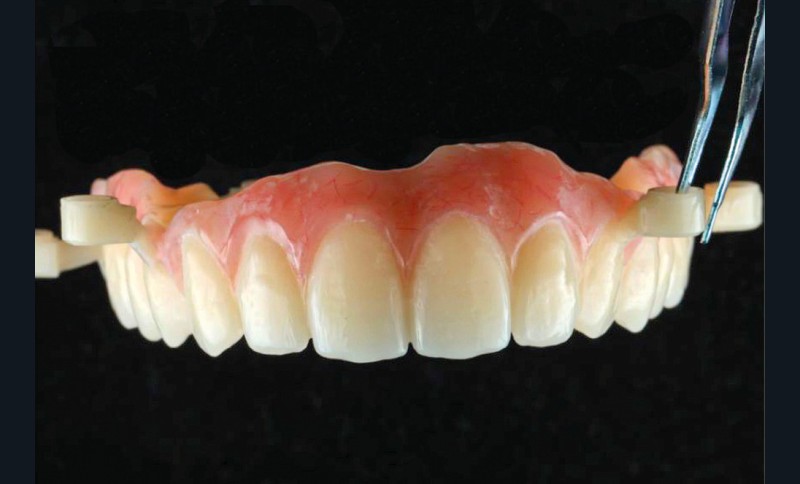

Après une extraction atraumatique des dents résiduelles, nous passons au 3e étage qui est le guide de forage stéréolithographique. La séquence de chirurgie Full guided est passée et les implants ont été torqués entre 40 et 50N.cm2 (fig. 6, 7, 8). Cette stabilité primaire dans les sites d’extraction et des sites greffés a permis la mise en charge immédiate du bridge complet provisoire. Des études cliniques [3, 4, 5] ont montré que la mise en charge immédiate dans les sinus greffés ne pose aucune contre-indication. Le 4e étage est donc celui du bridge provisoire transvissé à l’étage de base et solidarisé en bouche par l’intermédiaire de cylindres provisoires sur piliers MUA, avec une colle duale (GC-LinkForce). L’espace entre les implants et l’alvéole a été comblé par une xénogreffe (Bio-Oss Geistlich). Les profils d’émergence sont travaillés et parfaitement polis. Enfin, le bridge est mis en place, torqué à 20.cm2, équilibré et les consignes postopératoires ont été rappelées à la patiente (fig. 9 et 10).